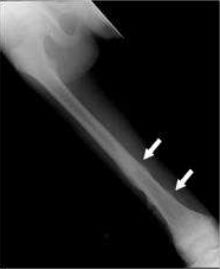

74.13歲男國中生最近覺得右腳膝蓋附近偶爾隱隱作痛,且疼痛的時間越來越長,晚上睡覺時症狀也很明顯,附 圖為下肢X光攝影,最可能的診斷為何? (A)fibrous dysplasia (B)aneurysmal bone cyst (C)osteogenic sarcoma (D)eosinophilic granuloma